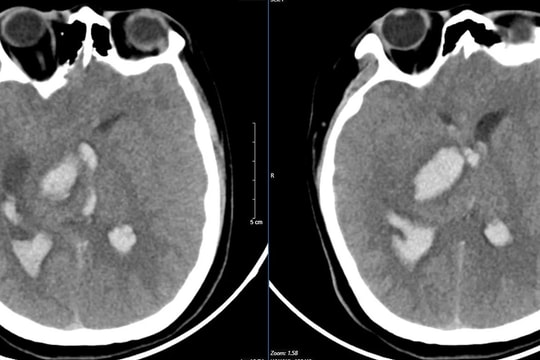

Nhầm lẫn với tiền đình, người phụ nữ mắc hội chứng thần kinh hiếm gặp

Gặp triệu chứng chóng mặt, tê bì tay chân, mất thăng bằng, người phụ nữ chủ quan nghĩ mình bị tiền đình, tuy nhiên căn nguyên lại là một hội chứng thần kinh nguy hiểm và hiếm gặp.

“Giải thoát” nữ bệnh nhân khỏi bệnh rối loạn phổ viêm tủy thị thần kinh thể hiếm gặp

Bệnh viện Đa khoa tỉnh Phú Thọ thông tin về việc đơn vị vừa điều trị thành công cho một trường hợp rối loạn phổ viêm tủy thị thần kinh thể hiếm gặp.